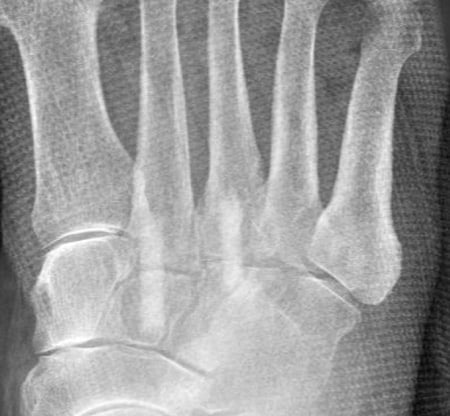

CT präoperativ

Zeigt deutliche Arthrose im TMT Gelenk.